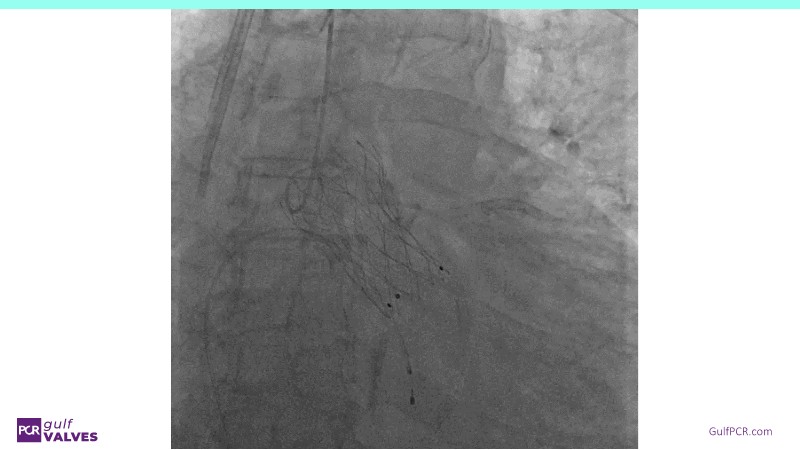

Discover a selection of cases showcasing the key features of the Navitor Valve System and its clinical applications. This session explores auxiliary access, the use of Navitor in alternative access and complex PCI, its performance in challenging peripheral anatomies, and innovative outcomes with the Vantage 30D system.